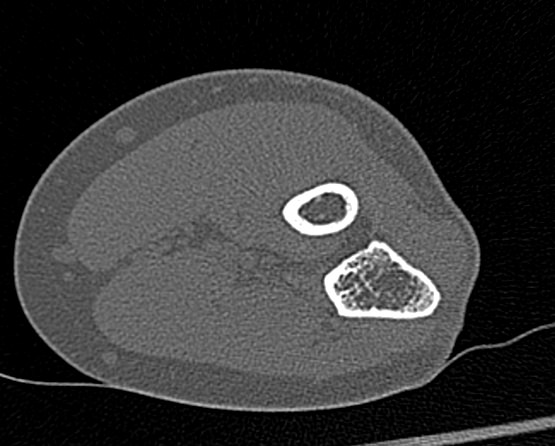

Одним из наиболее информативных методов исследования локтевого сустава является мультиспиральная компьютерная томография. Мультиспиральная КТ локтевого сустава позволяет оценить состояние костных структур и капсульно-связочного аппарата сустава. В отличие от обычного рентгена, при котором изображения накладываются друг на друга, мультиспиральная компьютерная томография с помощью рентгеновских лучей сканирует исследуемую область в разных плоскостях, делая множество тончайших срезов и преобразуя данные в цифровые трехмерные изображения.

Костная ткань хорошо поглощает рентгеновские лучи, поэтому кости ярко визуализируются на снимках КТ. Компьютерная томография в первую очередь востребована в ортопедии и травматологии. Методика широко применяется для диагностики костной патологии. С помощью КТ можно оценить плотность костной ткани и выявить косвенные признаки остеопороза. В случае перелома можно определить точную локализацию костных отломков, что особенно важно при планировании оперативного вмешательства и в послеоперационном периоде для наблюдения за процессом восстановления. КТ также помогает в диагностике различных артритов и артрозов.

- Что покажет КТ локтевого сустава

Что покажет КТ локтевого сустава

- врожденные особенности строения;

- сокращение плотности костей при остеопорозе;

- воспалительные процессы не только в самом суставе, но и в тканях, которые окружают его;

- переломы и трещины костей;

- дегенеративно-дистрофические изменения;

- гнойные процессы;

- инородные тела

- новообразования костей и мягких тканей (не только первичные опухоли, но и метастазы).